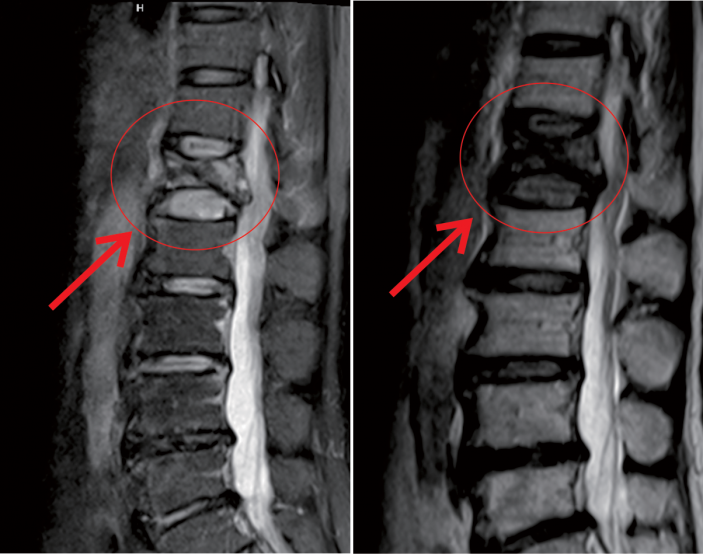

△術前MR顯示,第一腰椎壓縮性骨折

△術後,病變的椎體迅速恢複了功能